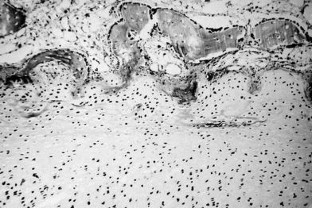

Fig. 3